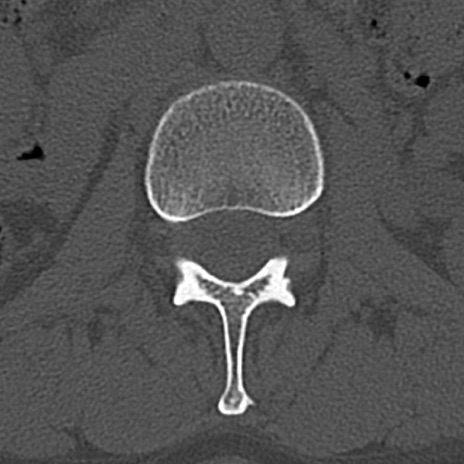

腰椎CT

横断像と矢状断像